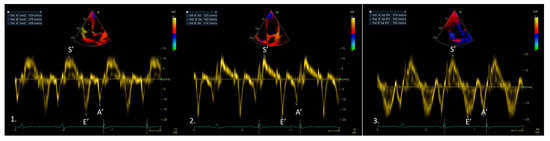

3. Tissue Doppler Imaging Characteristics